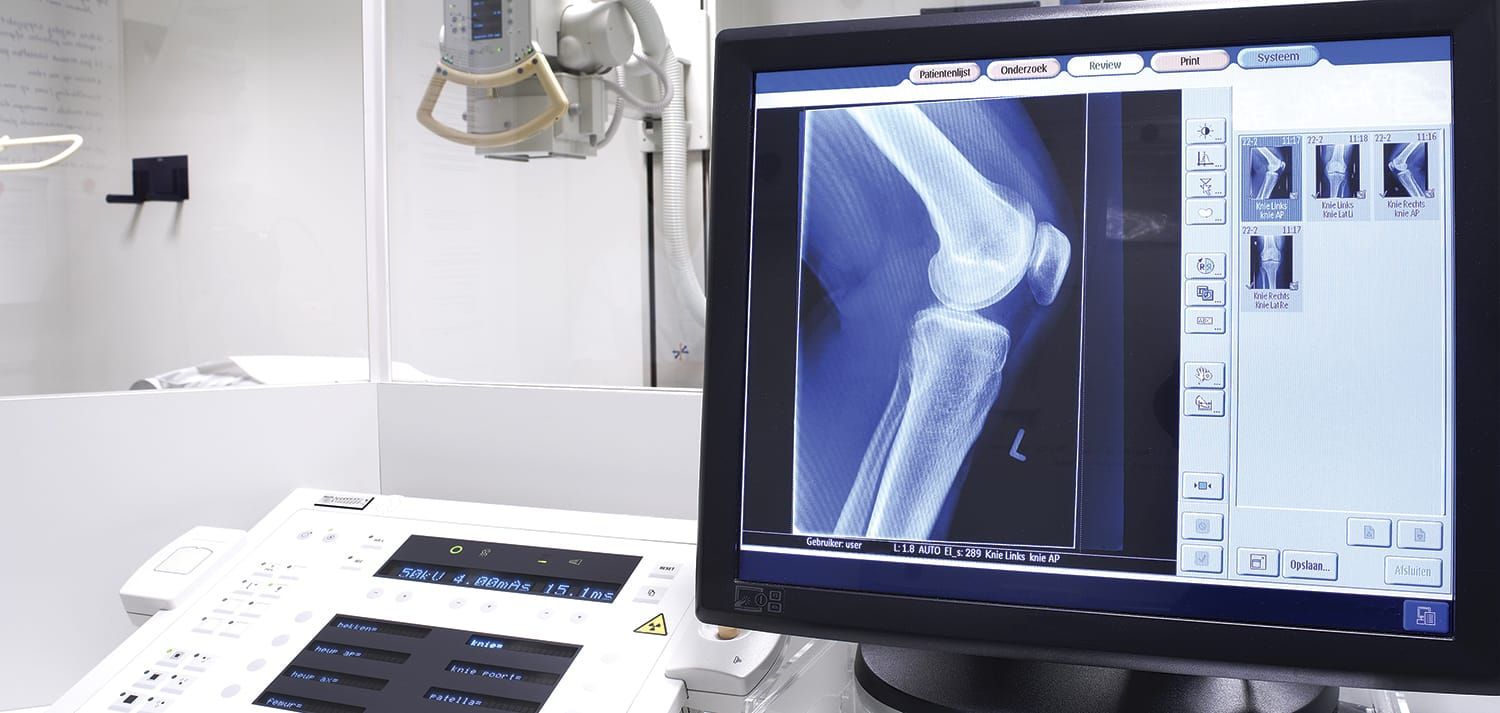

Guide To Knee Pain & Injuries

When you feel a pain in your knee, your mind might quickly go to the worst-case scenario. That reaction might be warranted or not. Here’s a simple guide to help jiu-jitsu practitioners know when it’s OK to keep training, when to be a little cautious and when it’s necessary to stop and seek immediate treatment. While this is just a guide with a few examples of some common scenarios, any injury should be evaluated by a licensed healthcare provider and treated accordingly.